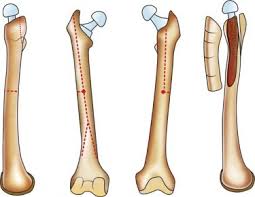

This nerve is at risk for injury with a humeral shaft fracture and can result in wrist drop.

What is the radial nerve?